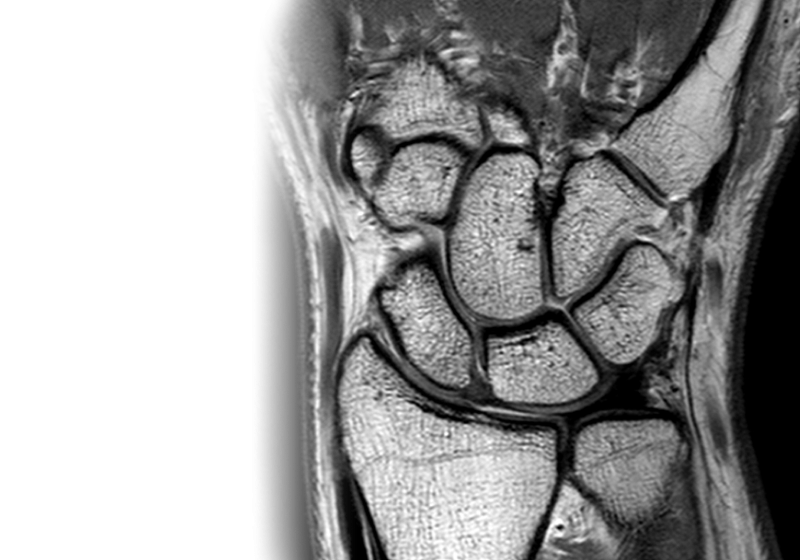

МРТ лучезапястного сустава МРТ лучезапястного сустава

МРТ лучезапястного сустава

Магнитно-резонансная томография лучезапястного сустава – важный метод исследования, который позволяет оценить состояние лучезапястного сустава.